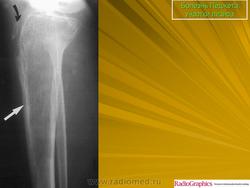

Литическая фаза.

Смешанная фаза.

Бластная фаза

Принято различать три фазы развития П. б.: очаговая интенсивная резорбция кости (остеолитическая, или деструктивная, фаза), смешанная фаза, когда наряду с рассасыванием кости идут процессы новообразования ее, и остеобластическая, или склеротическая, фаза с образованием типичных мозаичных структур.